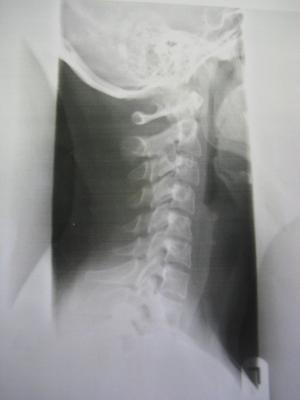

Heute war ich hier beim Durchgangsarzt,da momentan alle Orthopäden hier Urlaub haben bis nach Ostern und ich Probleme habe meinen Kopf vernünftig zu bewegen.Er hat Röntgenbilder gemacht und ich hab einen richtigen Schock bekommen.Das was ich vermutet habe,hat sich wohl bestätigt,es ist schlimmer geworden mit der Skoliose und ich muss sofort zu einem Orthopäden.Ich habe stärkere Schmerzmittel bekommen und mein Arzt meint,ich brauche wohl ein Korsett.....

Ich hab mal die Bilder vom Röntgen angehängt.Den Grad der Verkrümmung weiss ich leider noch nicht.Aber kann mir vielleicht jemand was zu den Bildern sagen?

forum_photo.jpg

forum_photo.jpg (10.91 KiB) 4237 mal betrachtet

Ja, Kiefer sieht wirklich schief aus.

Der Rücken sieht doch, was man auf den Bildern erkennen kann, gar net so schlimm aus.

Allerdings sieht man halt vom unteren Rücken nichts.